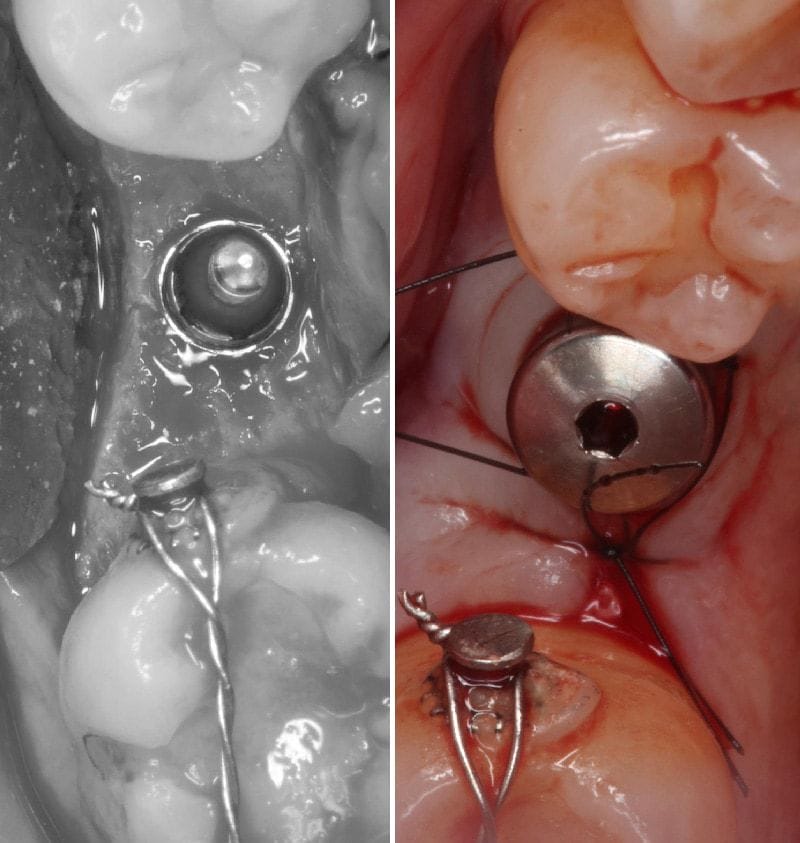

圖示:側窗式鼻竇增高術,箭頭為人工植牙處和側窗補骨粉處 圖示:補骨粉後覆蓋膠原蛋白再生膜,為牙周組織創造良好的再生復原空間

(上顎後牙區因骨質與骨量關係,植牙成功率一般而言較低。醫師會依照骨頭條件進行「側方開窗術」或「植牙孔處鼻竇增高術」來改善植牙條件。推薦可以參考 鼻竇增高術 – 上顎區植牙補骨法 進一步了解鼻竇增高術和手術後注意事項。)

左下第二大臼齒因為臨床牙齒太短,同次也進行 牙冠增長術,讓未來的假牙不易鬆脫,也能夠提升正式假牙的密合度。